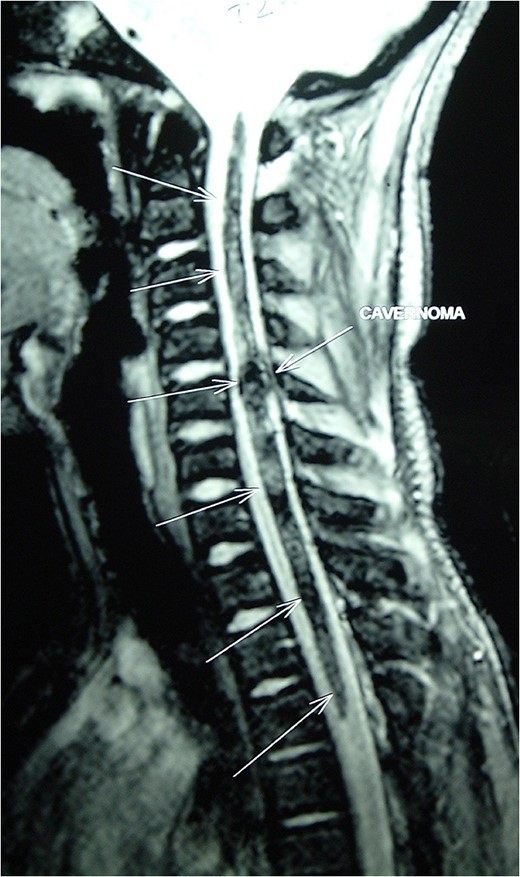

Magnetic resonance imaging (MRI) of the brain and spine showed multiple hypointense lesions in the brain and one mixed intense lesion with a hyperintense rim intrinsic to the spinal cord at the level of C5 with evidence of fresh bleeding (Figs 1–3). He was diagnosed with multiple cerebral cavernomas and an acutely bleeding spinal cavernoma. The patient was scheduled for a laminectomy and total excision of the spinal cavernoma and to control further hemorrhage. Bone removal was limited to the site of malformation. The lesion was identified by the bluish discoloration on the dorsal surface of the spinal cord (Fig. 4). A myelotomy was made over the discoloration and the lesion was excised inside out. Intraoperative evoked potential monitoring was not used for our procedure due to lack of availability.

MRI Spine (GRE T2WI) sagittal view shows a localized lesion within the spinal cord at C5 with a mixed intensity focus centrally and a surrounding low-signal ring typical of cavernous angioma with surrounding hemosiderin deposition.